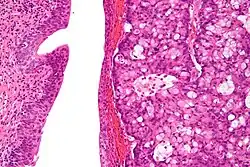

The urachus is also subject to neoplasia. Urachal adenocarcinoma is histologically similar to adenocarcinoma of the bowel. Rarely, urachus carcinomas can metastasise to other regions of the body, including pelvic bones and the lung.[7]

High magnification micrograph of a urachal carcinoma. H&E stain